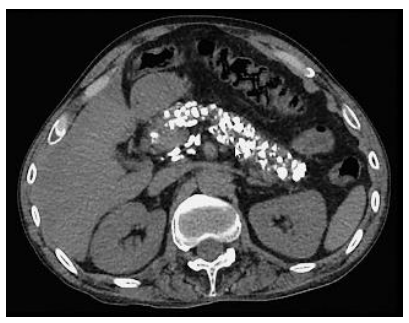

Homem, 45 anos, etilista por 10 anos. Na investigação de uma dor abdominal, realizou a TC abaixo.

Qual sintoma NÃO é esperado nessa situação?